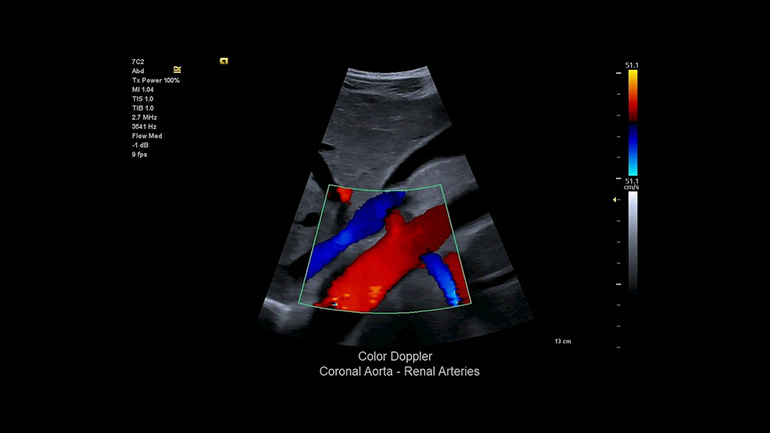

B-режим. Высокое контрастное разрешение и однородность изображений — отличное диагностическое качество. Цветовые допплеровские режимы. Надежность диагностики повышается благодаря высокочувствительному цветовому доплеровскому режиму при снижении артефактов яркости цвета.

Цветовые допплеровские режимы. Надежность диагностики повышается благодаря высокочувствительному цветовому доплеровскому режиму при снижении артефактов яркости цвета.Специализированные опциональные приложения